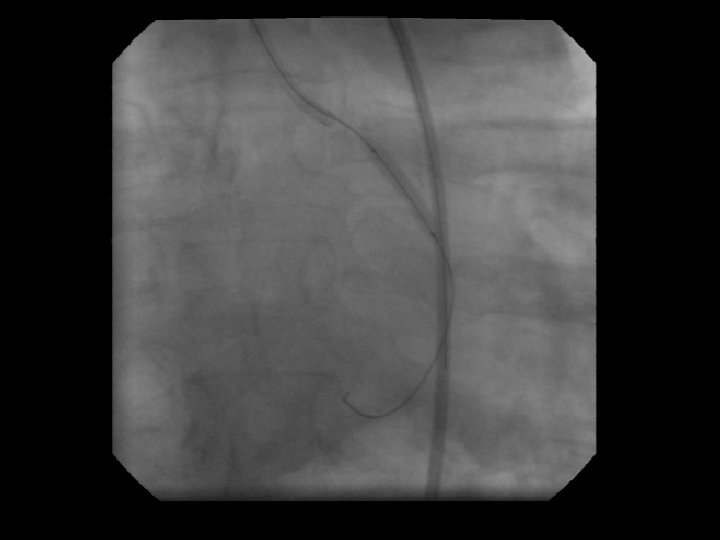

Coronary Angiography for PCI • Get a Clear View of vessel and lesion anatomy including side branches. • Better yet, get two high quality orthogonal views. • If the wire is not going properly in your “best view” look in a second view.

Proximal Ramus Stenosis